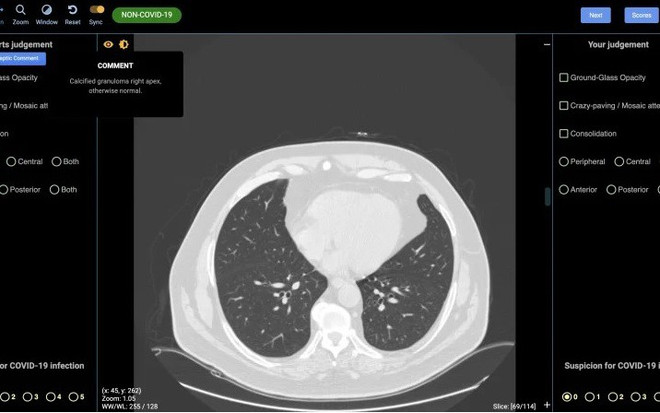

Australia phát triển công cụ AI hỗ trợ phát hiện người mắc COVID-19 ảnh 1Ảnh chụp CT phổi người không mắc Covid-19. (Nguồn: Detected-X)

CovED cho phép chẩn đoán chính xác những người nhiễm SARS-CoV-2 nhờ phương pháp phân tích hình ảnh chụp cộng hưởng từ (CT) phổi của bệnh nhân.

Công ty khởi nghiệp DetectED-X, liên kết với Đại học Sydney, đã công bố một công nghệ mới, gọi là CovED, cho phép chẩn đoán chính xác những người nhiễm SARS-CoV-2 nhờ phương pháp phân tích hình ảnh chụp cộng hưởng từ (CT) phổi của bệnh nhân.

Giám đốc điều hành DetectED-X, Giáo sư Patrick Brennan, cho biết công nghệ AI mới hỗ trợ các chuyên gia hình ảnh trong lĩnh vực y tế, đọc hiểu và phân tích cặn kẽ những ảnh hưởng ở phổi của người được chụp CT, dựa trên một hệ thống AI có khả năng kết luận chính xác về việc liệu người được chẩn đoán có bị nhiễm SARS-CoV-2 hay không. Mọi thao tác và kết quả chuẩn đoán sẽ có sau khoảng một giờ hoạt động.